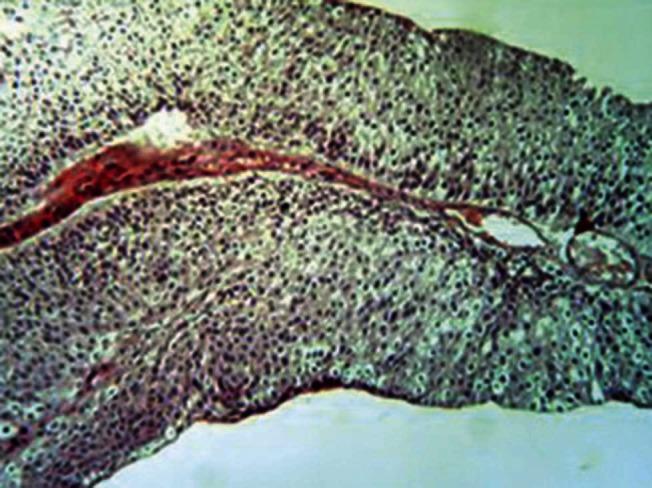

This study was retrospectively designed. Forty-nine cystoscopy specimens of urothelial carcinoma of the bladder were retrieved from the archival materials of the Specialized Surgical Hospital and Al-Khadhmiya Teaching Hospital in Baghdad for the period from January 2010 to June 2011. Three sections of 5-μm thickness were taken from each case. One section was stained with Hematoxylin and Eosin; the other two were stained immunohistochemically with CA19.9 and CD10.

本研究为回顾性设计。从巴格达专科医院和哈迪米亚教学医院2010年1月至2011年6月的存档材料中检索了49例膀胱尿路上皮癌的膀胱镜检查标本。每个病例取3张厚度为5μm的切片。一张切片用苏木精和伊红染色;另外两张用CA19.9和CD10进行免疫组化染色。